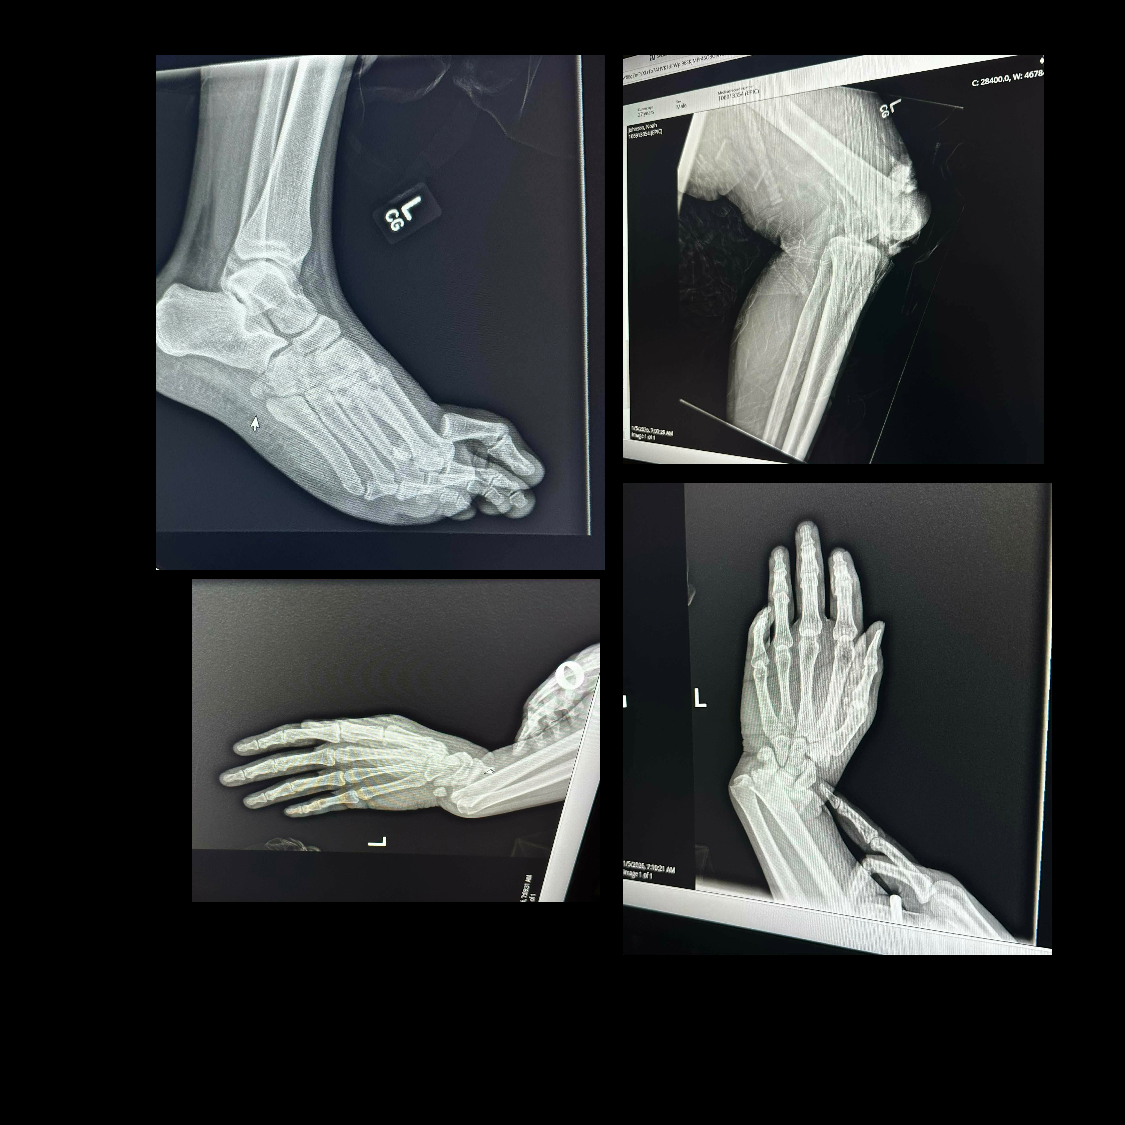

As a result of the crash, Noah suffered significant trauma to both of his legs and ankles, as well as serious injuries to his wrists, lungs, and spine. These injuries are life-altering. Doctors have made it clear that his recovery will be long, painful, and complex, involving additional surgeries, extensive rehabilitation, and months — possibly longer — of limited mobility. At just 27 years old, Noah is now facing the reality that his physical abilities, independence, and daily life have been permanently affected.

The full outcome is still uncertain, and his medical journey is far from over. While doctors continue to work tirelessly to repair the damage, the financial burden continues to grow. Unfortunately, Noah’s insurance will not cover all of the medical expenses associated with these traumatic injuries, surgeries, rehabilitation, and future care.